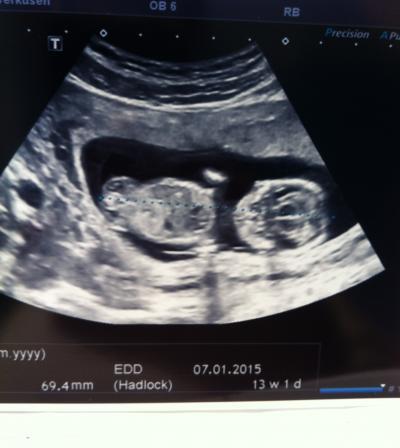

Hallo Ihr Lieben, nachdem ich letzte Woche im Urlaub war und dort in den 4. Monat gerutscht bin, hatte ich heute das Ersttrimester-Screening. Im ca. 15 minütigen Ultraschall waren glückerlichweise keine Auffälligkeiten und der Zwerg hat richtig gestrampelt und Arme und Beine bewegt. Mittlerweile knapp 7 cm Schädel-Steiß-Länge und Nackenfalte war unauffällig.

Habe auch ein schönes Bild bekommen...